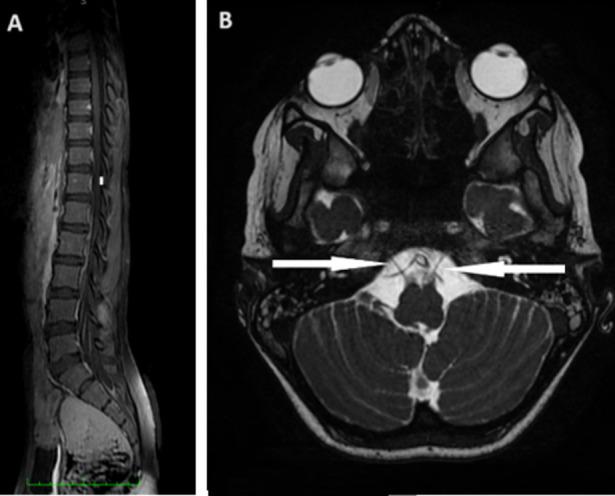

Guillain-Barré syndrome/Miller-Fisher syndrome (GBS/MFS) overlap syndrome is an extremely rare variant of Guillain-Barré syndrome (GBS) in which Miller-Fisher syndrome (MFS) coexists with other characteristics of GBS, such as limb weakness, paresthesia, and facial paralysis. We report the clinical case of a 12-year-old patient, with no pathological history, who acutely presents with ophthalmoplegia, areflexia, facial diplegia, and swallowing and phonation disorders, followed by progressive, descending, and symmetrical paresis affecting first the upper limbs and then the lower limbs. An albuminocytological dissociation was found in the cerebrospinal fluid study. Magnetic resonance imaging of the spinal cord showed enhancement and thickening of the cauda equina roots. The patient was treated with immunoglobulins with a favorable clinical outcome.

格林-巴利综合征/米勒-费舍尔综合征(GBS/MFS)重叠综合征是一种极为罕见的格林-巴利综合征(GBS)变异型,其中米勒-费舍尔综合征(MFS)与 GBS 的其他特征同时存在,如肢体无力、感觉异常和面瘫。我们报告了一例 12 岁无病理史患者的临床病例,其急性出现眼肌麻痹、反射消失、面瘫和吞咽及发音障碍,随后进行性、下行性和对称性无力影响上肢,然后影响下肢。脑脊液研究发现蛋白细胞分离。脊髓磁共振成像显示马尾神经根增强和增厚。该患者接受免疫球蛋白治疗,临床结果良好。